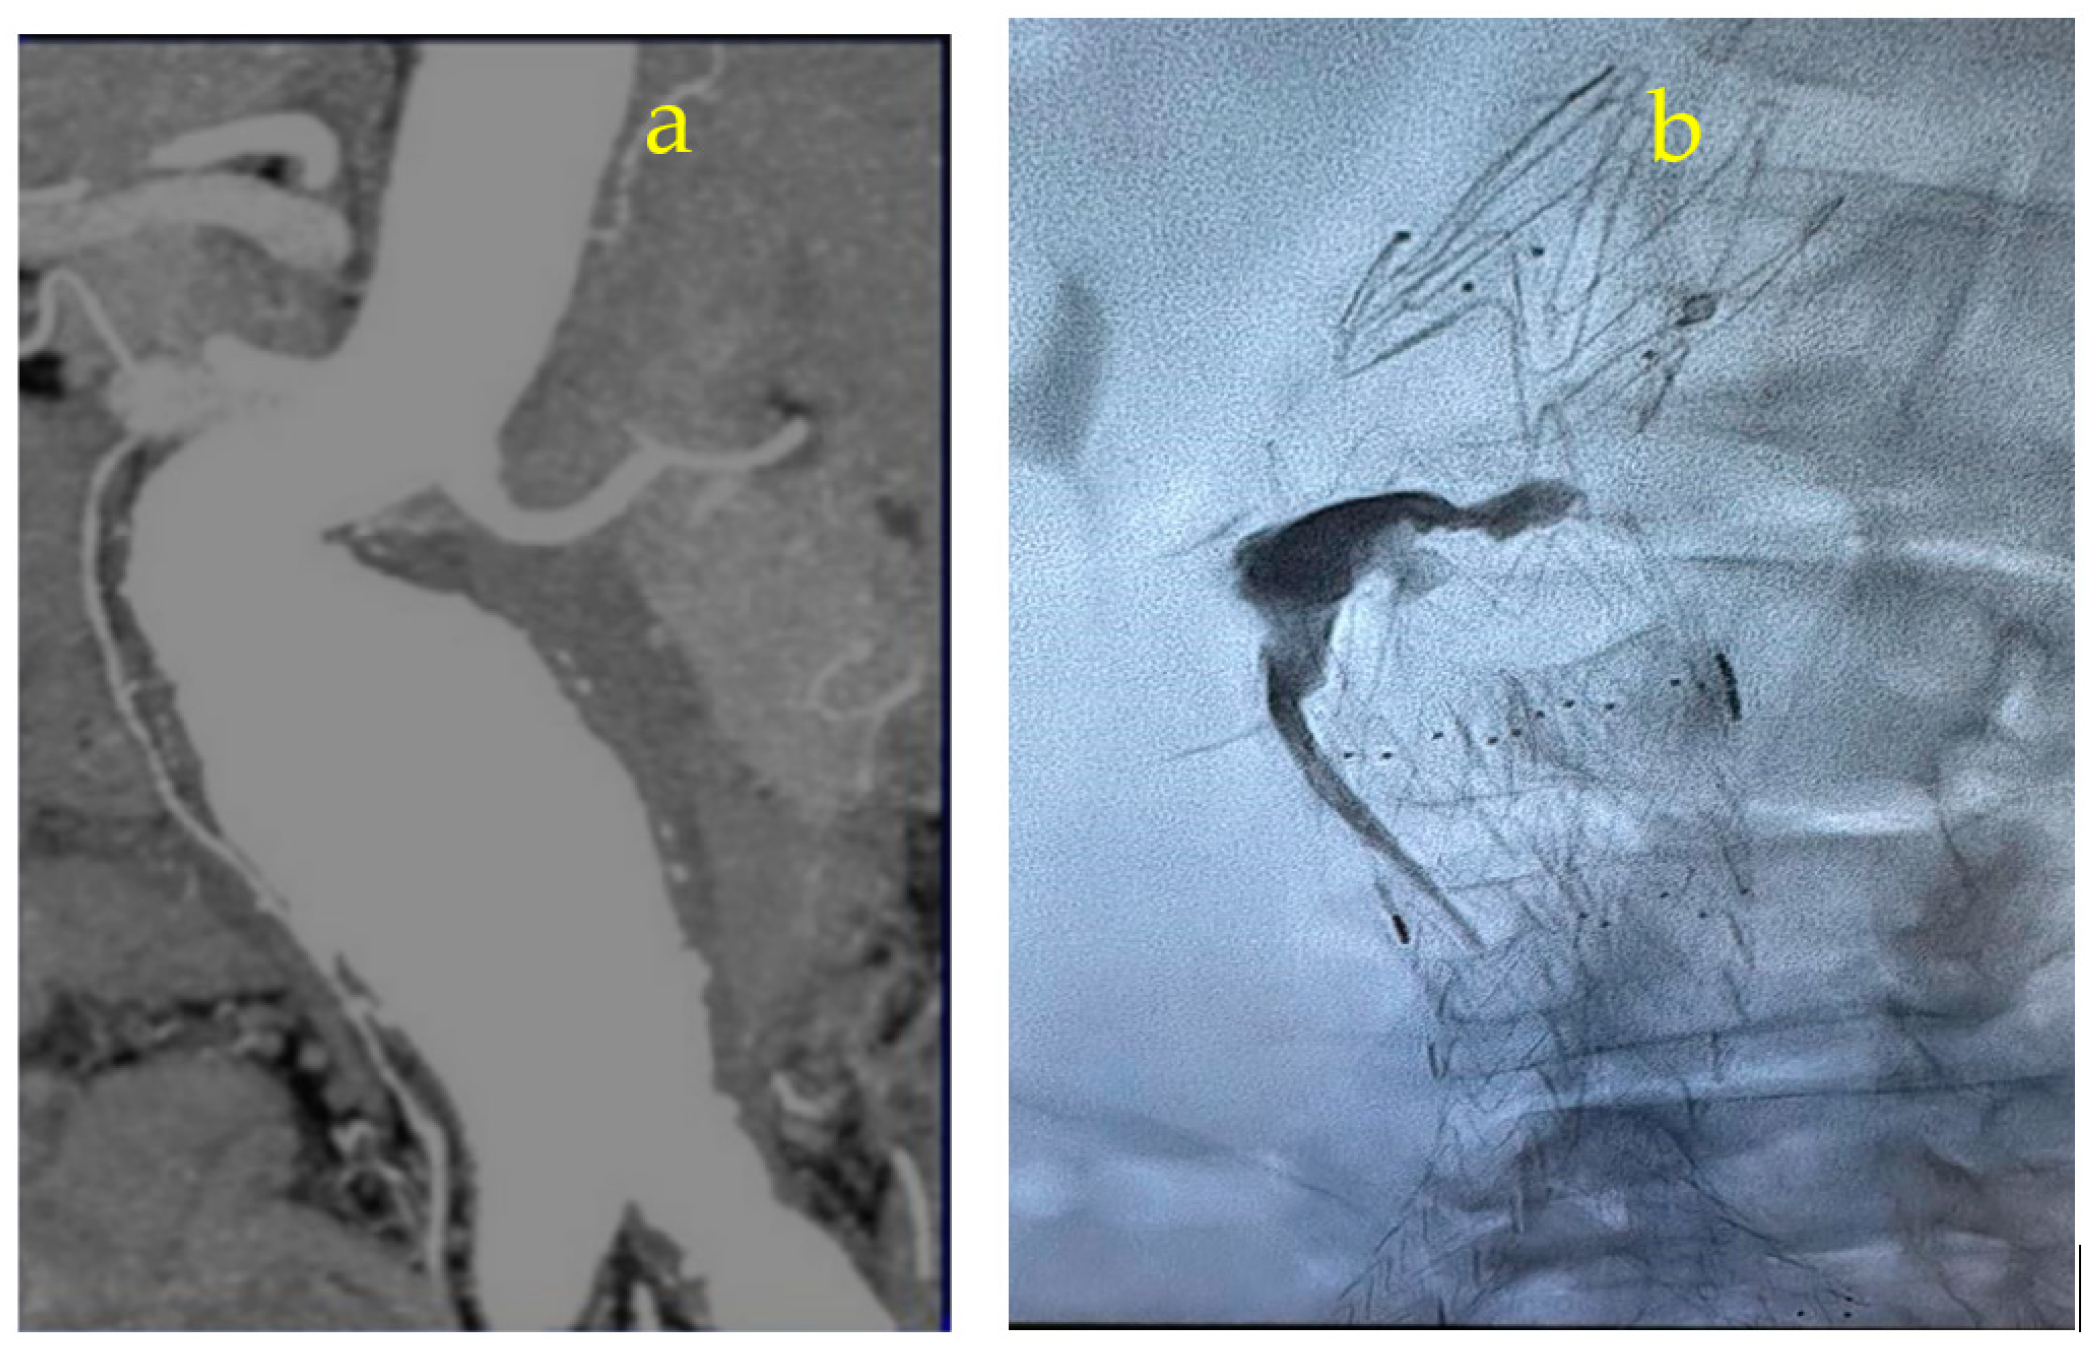

Appendix A.1. Clinical Case 1: Right Renal Visceral Arteriovenous Malformation